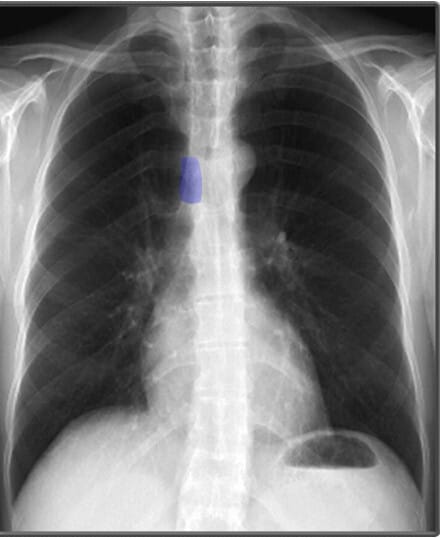

위 사진에서 남색으로 표시된 부분은 Spinous Process 입니다.

Landmarks in Chest X-ray (PA view)

폐와 심장 및 흉곽 구조물을 분석할 때 유용한 해부학적 지표로는 유방 음영(breast shadows), 심장 크기(cardio-thoracic ratio), 늑골횡격막각(costophrenic angles), 위 기포(gastric bubble) 등이 있습니다.

| 심장 크기 (Cardiac Width) |

| ✅ 정상적인 심장 크기는 흉곽 폭의 50% 이내여야 하며, 이를 심흉비(cardiothoracic ratio, CTR)라고 합니다. 비정상적으로 증가하면 심부전 또는 심장 비대의 가능성을 고려해야 합니다. |

| 늑골횡격막각 (Costophrenic Angles) |

✅ 폐 하부와 횡격막이 만나는 부분으로, 정상적으로 뚜렷하고 날카로워야 합니다. ✅ 둔해지거나 소실되면 흉수(pleural effusion) 가능성을 시사합니다. |

| 위 기포 (Gastric Bubble) |

| ✅ 좌측 횡격막 아래에서 나타나는 공기음영으로, 정상적인 해부학적 지표 중 하나입니다. 위치가 변하면 장폐색 등 복부 문제를 의심할 수 있습니다. |

종격동(mediastinum)은 심장과 주요 혈관, 기관(trachea) 등이 위치하는 공간으로, 이들의 크기와 모양을 분석하는 것이 중요합니다.

| 대동맥궁 (Aortic Arch) |

| ✅ 좌측 폐문(hilus) 위에서 둥글게 보이며, 확장되거나 비대해지면 대동맥류 또는 고혈압성 변화 가능성을 고려해야 합니다. |